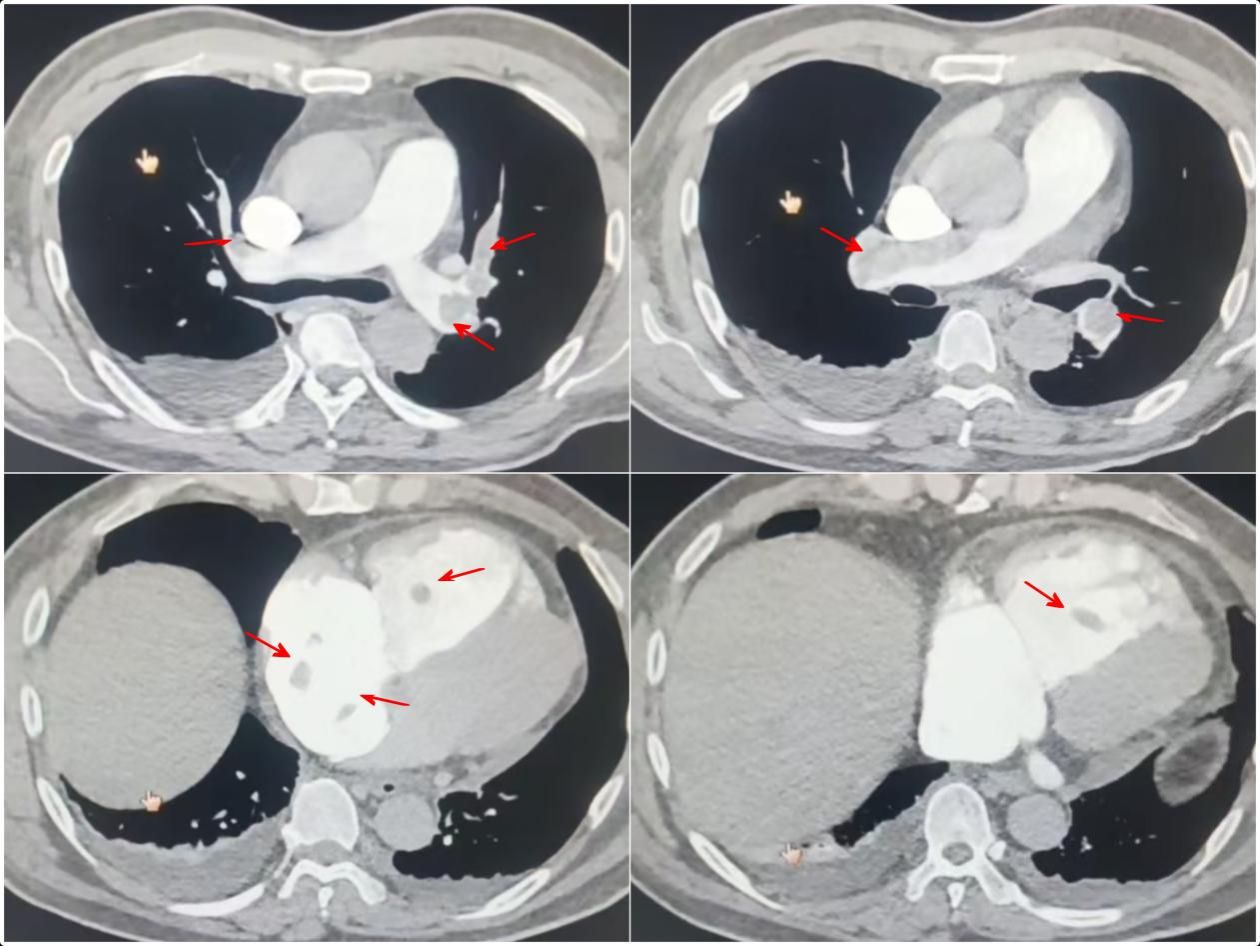

图1 术前肺动脉CTA显示肺动脉及右心房、右心室内血栓

患者为54岁的中年男性,入院3周前无明显诱因出现胸闷、气短症状,在当地卫生所按“肺部炎症”治疗后效果不佳。入院4天前患者突发短暂晕厥,此后就诊于当地市医院,行下肢静脉超声提示“右下肢深静脉血栓形成”,肺动脉CTA提示“双肺动脉多发血栓形成”,更危险的是,心脏超声发现患者右心房、右心室内已形成多发活动性血栓,其中最大者达5.1*2.1cm,随心跳剧烈摆动,宛如一颗随时可能脱落、导致患者猝死的“心脏内炸弹”。当地医院紧急为其植入下腔静脉滤器防止深静脉血栓继续脱落导致更大面积的肺栓塞,并迅速转诊至我院。

我院接诊时患者已出现呼吸衰竭及心功能衰竭表现,病情极度凶险。高峰教授指出:“患者已形成完整的‘下肢深静脉血栓--右心血栓--肺栓塞’的危机链条,右心腔内如此巨大的活动性血栓极其危险,它脱落后可瞬间完全堵塞肺动脉主干,引发患者猝死;而目前药物治疗后,呼吸及循环功能仍在进一步恶化,患者已是危在旦夕,唯一的生机在于立即手术清除肺动脉及心腔内的血栓”。